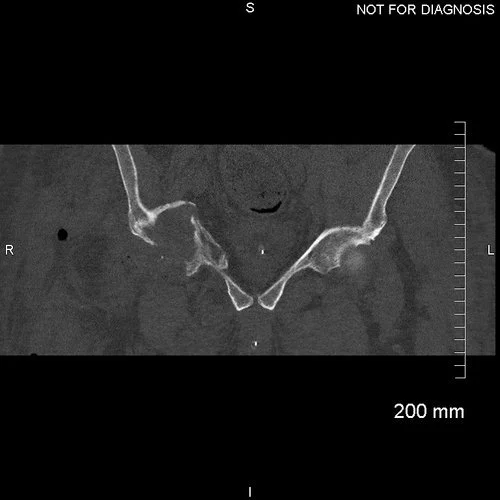

Coronal CT demonstrating an adequately seated implant with sufficient screws fixed to acetabular bone.

Anteroposterior and lateral plain radiographs taken 9-months after Mitchell’s operation. There is no radiographic evidence of any implant migration and Mitchell was happy with the result in clinic.